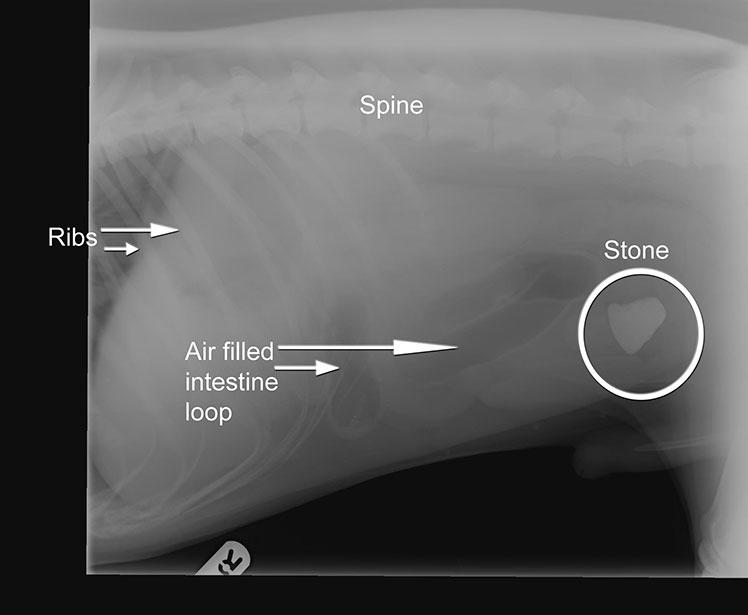

Arky is a gorgeous 9 month old red setter. He presented to us feeling vey poorly and being regularly sick. We admitted him into the practice to do some tests - blood samples and x-rays. The x-ray we took is below.

The white item you can see in his abdomen is a stone! Arky had willingly eaten this stone! It had made its way through his stomach, through the top of his intestines before getting stuck halfway through his guts. At this point things became very serious. If this stone was left where it was Arky would become even more ill. So we took him straight to theatre where we removed the stone surgically.

Arky stayed with us for three days whilst we got him going again - the care these patients receive after these major operations is absolutely vital to success. Our nurses very carefully fed him and nursed him back to form. Unfortunately sometimes dogs that eat ‘foreign bodies’ likes stones can die, so it is extremely serious. To everyone’s delight though Arky has made a full recovery and is now back at home getting up to more mischief!